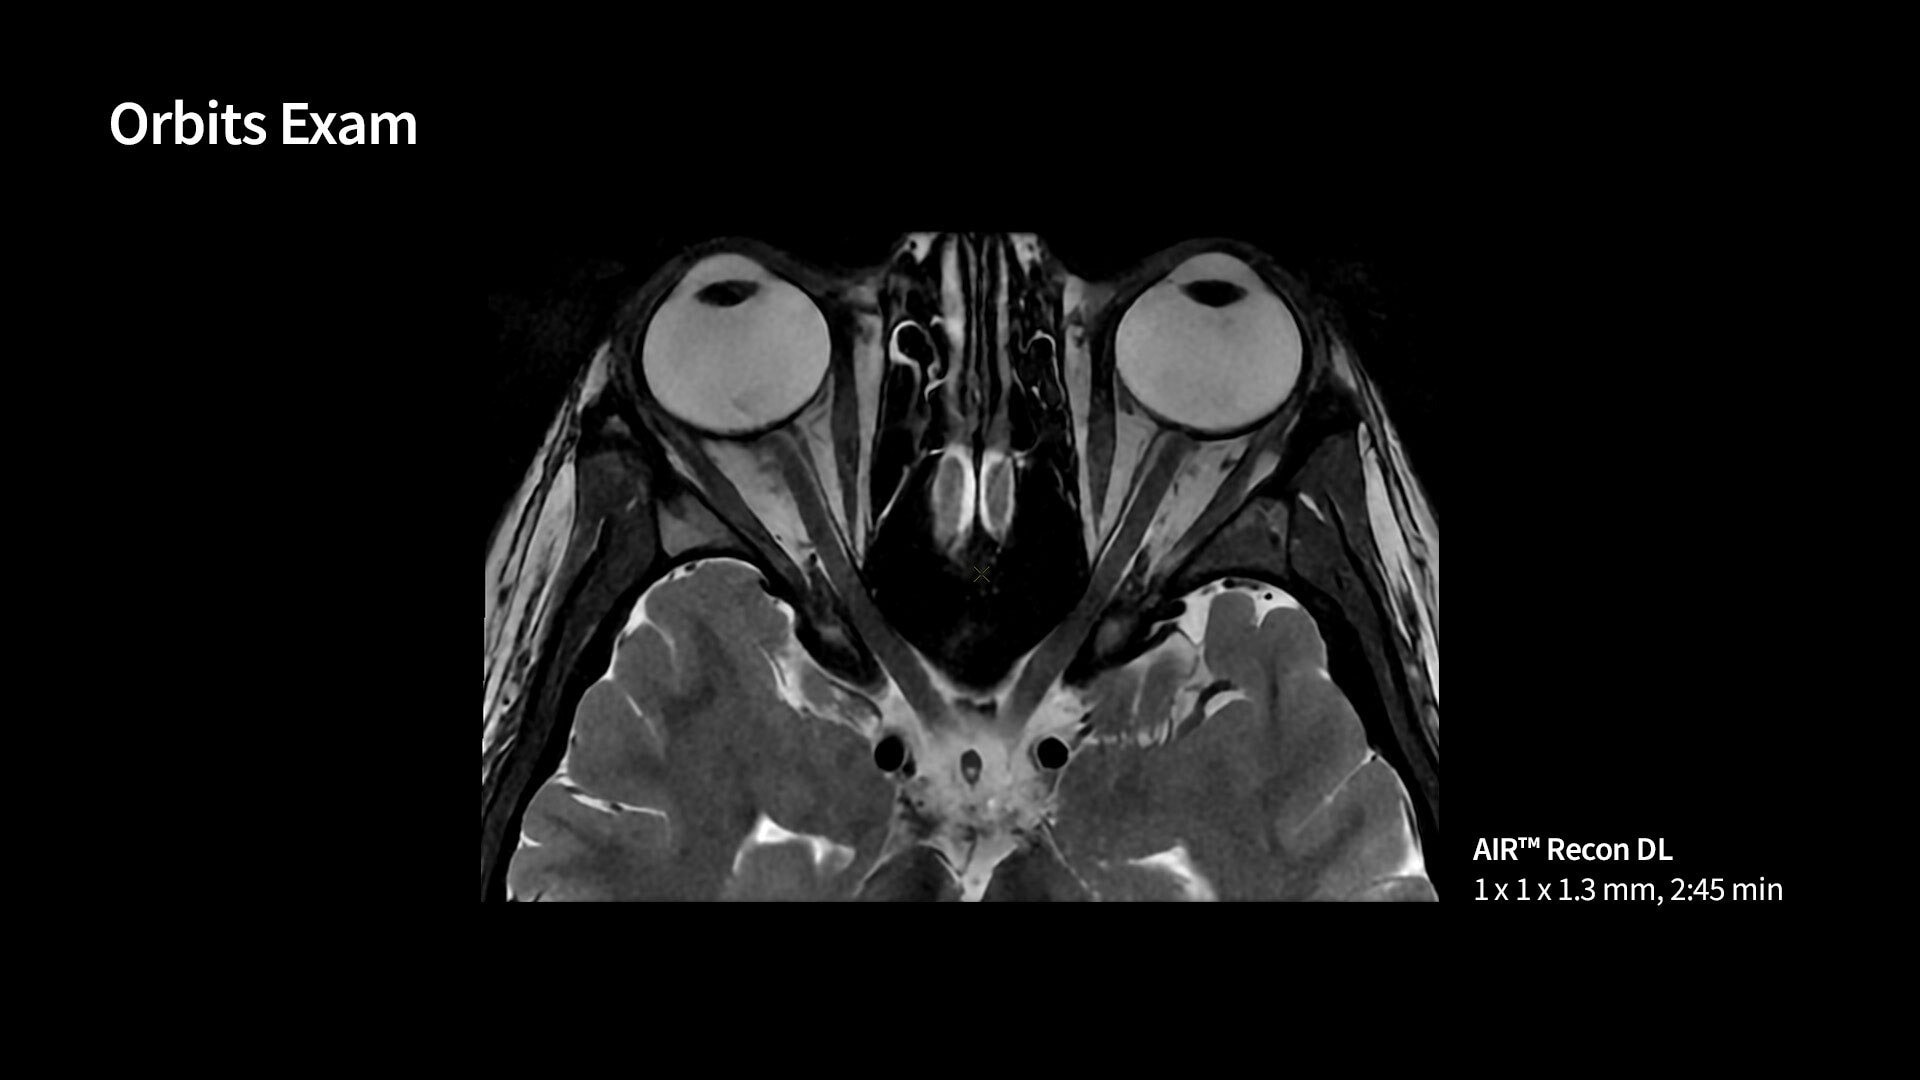

<p>AIR Recon DL</p>

Learn more ico-caret-right

MR image reconstruction with AIR Recon DL

Evolve your MRI scanner's capabilities: experience exceptional image quality without compromising scan time.